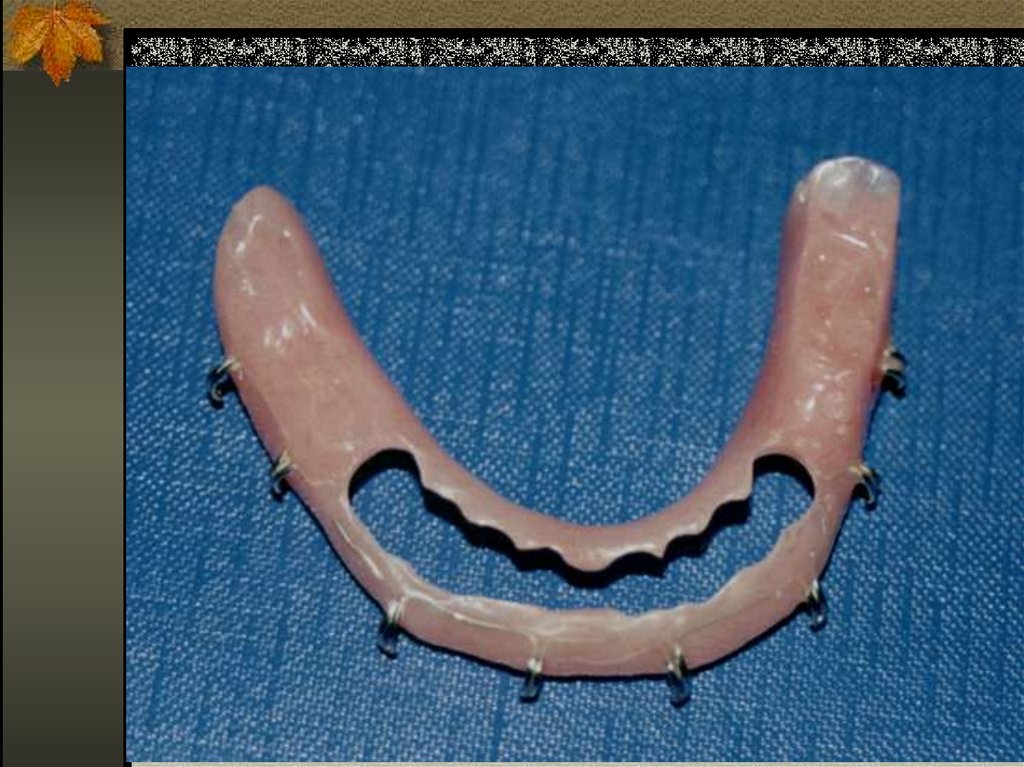

19. GUNNING SPLİNT

20.

21. DÖKÜM REHBER APAREYİ